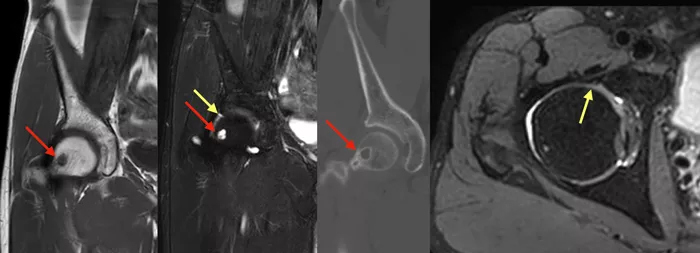

股関節MRIでは骨皮質下透亮像に一致した部位にT1強調画像でlow、STIR画像でhighの信号変化を認め、前上方の股関節唇に損傷を認めた。骨頭荷重面には信号変化を認めなかった(写真3)。

単純CTでは、骨皮質下透亮像の部位には皮質骨の破壊や肥厚は認めず(写真3)、腫瘍性病変ではなく、herniation pitであると考えられた1)

写真3

MRIとCTでHerniation pitを認める(赤矢印)。股関節唇内に信号変化(黄矢印)を認め、損傷が示唆される。